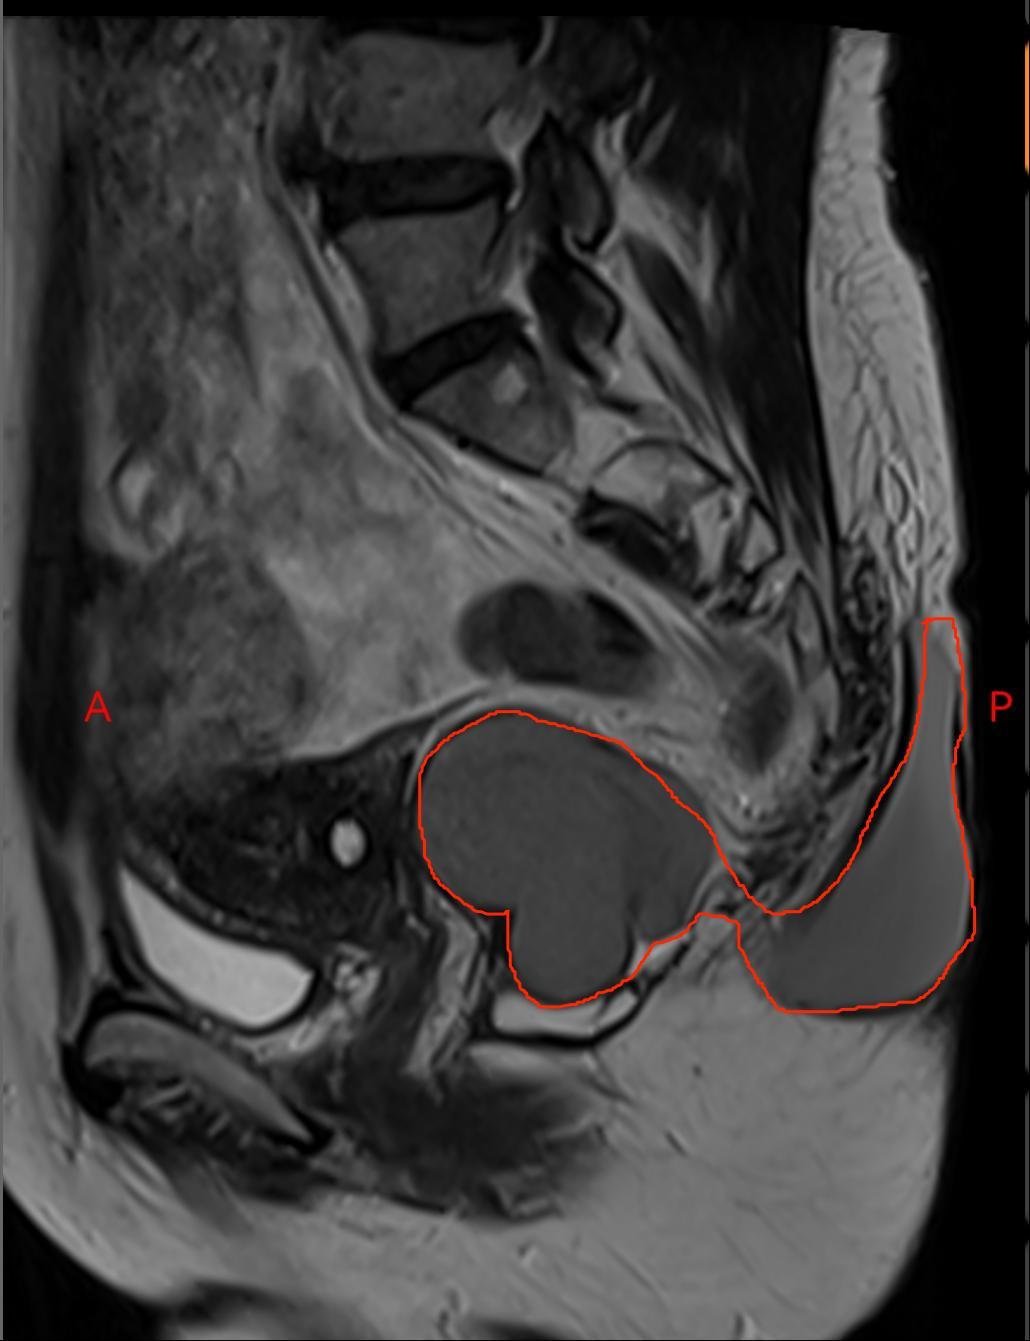

从磁共振上看,这个包块有两部分,像个葫芦一样,肚子里面一半,外面一半

外面的那一半像是从尾骨里面挤出来的一样,与肛门周围的肌肉和直肠关系非常密切。

这已经不是一个简单的门诊囊肿切除小手术了,而是一个 非常特殊 的骶前发育性囊肿,需要住院手术治疗。